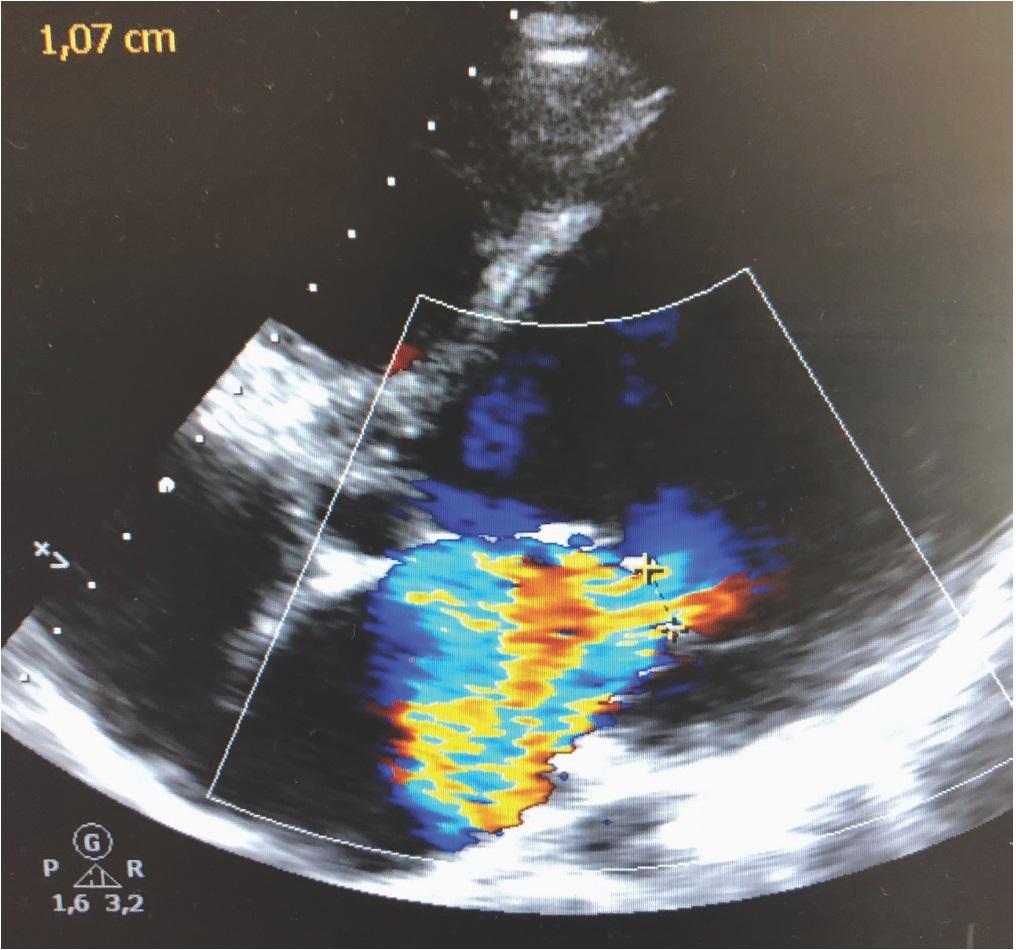

Figure 1